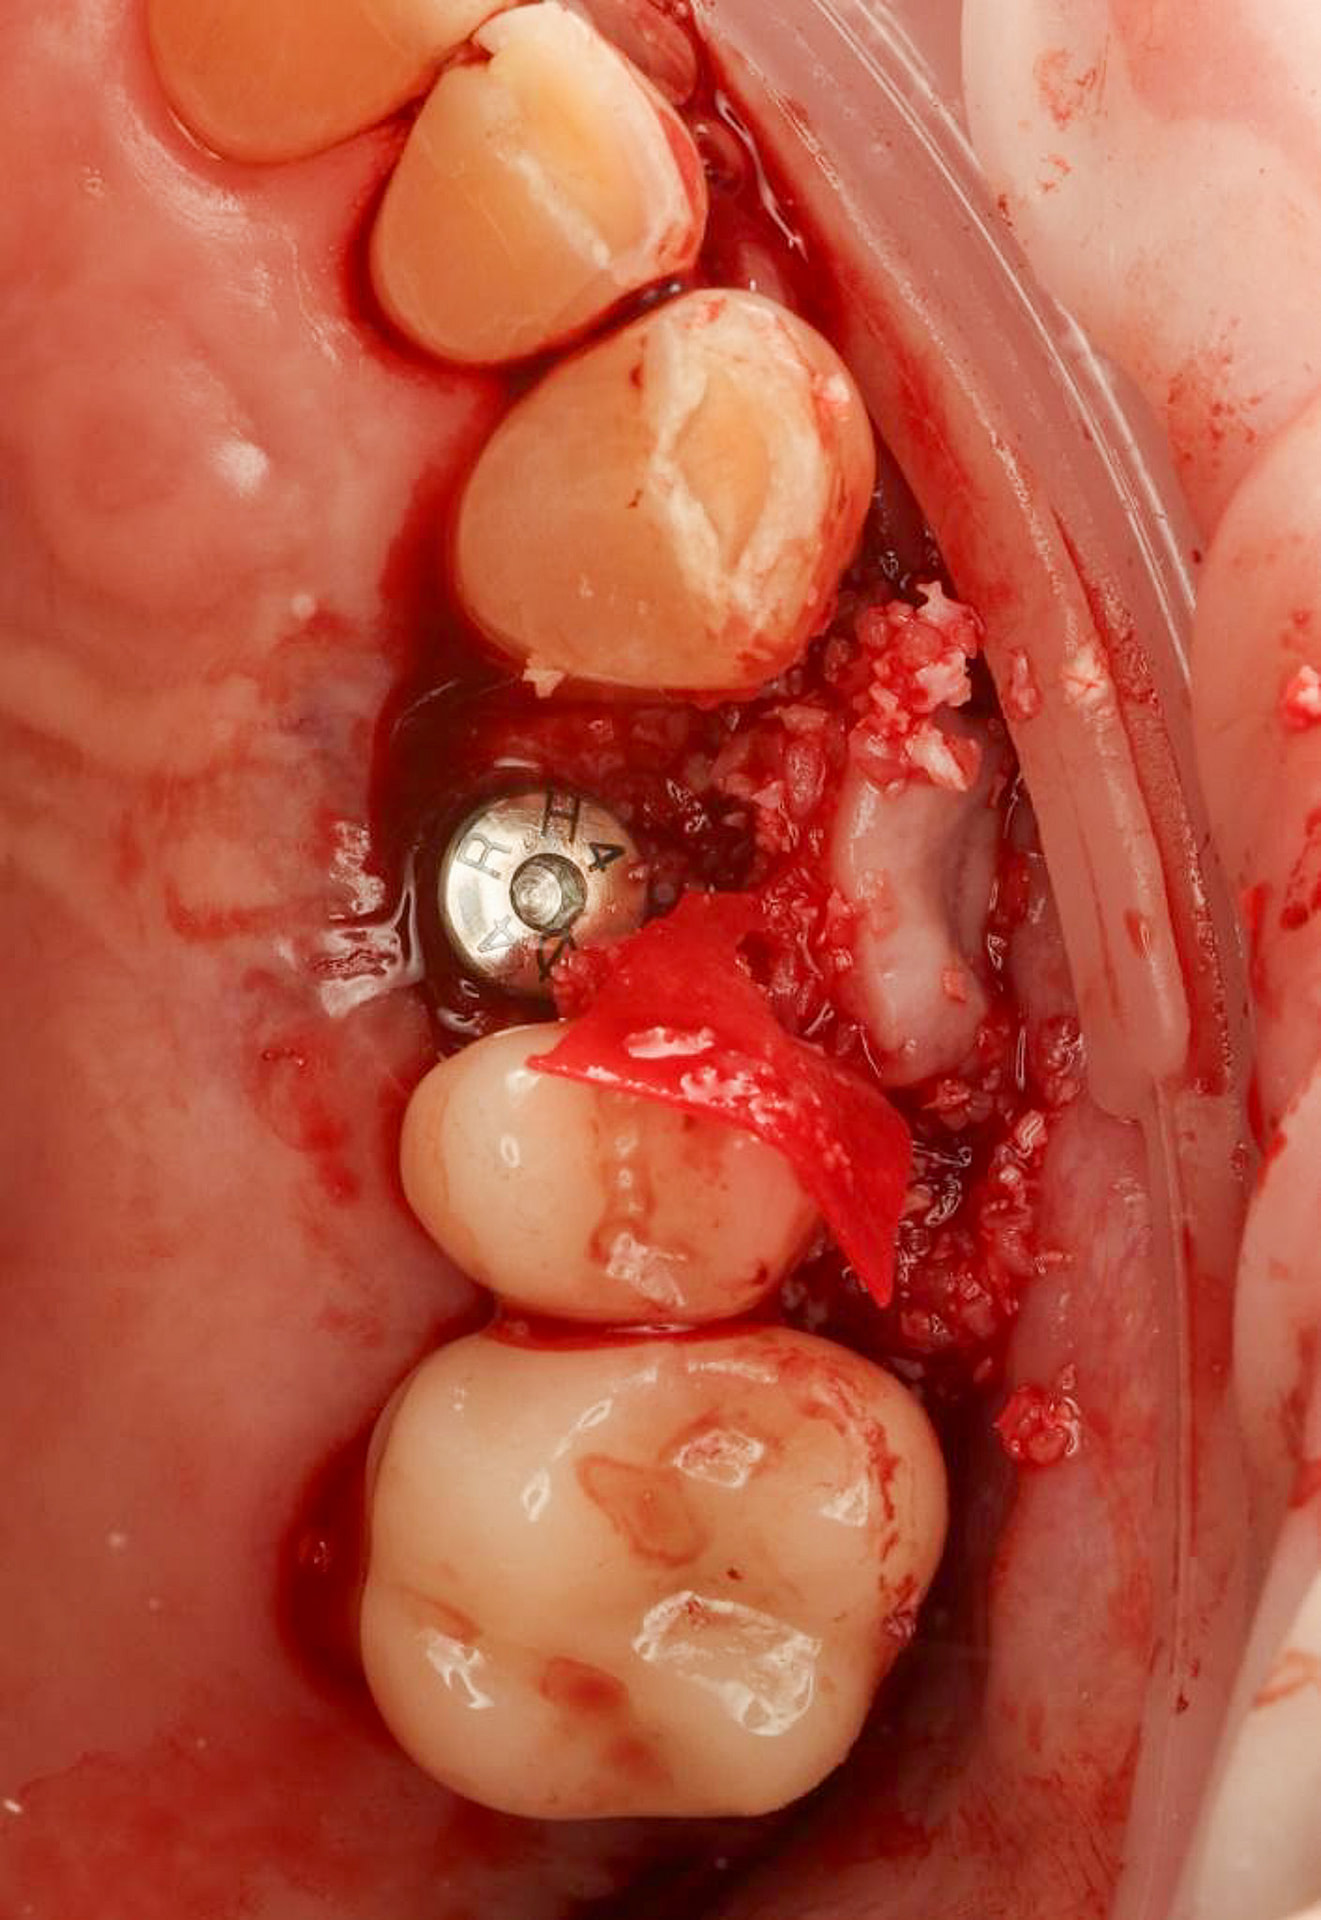

A custom surgical guide was designed and 3D printed, incorporating all the critical information from the virtual planning. The implant surgery was performed under local anesthesia, with the surgical guide firmly in place to ensure accurate implant placement. Bone grafting was performed to address the bony defect and promote optimal healing.

The Osstem OneGuide kit is used with a fully guided osteotomy and implant placement.

Osstem TSIII D4 x H10mm implant on NoMount driver.